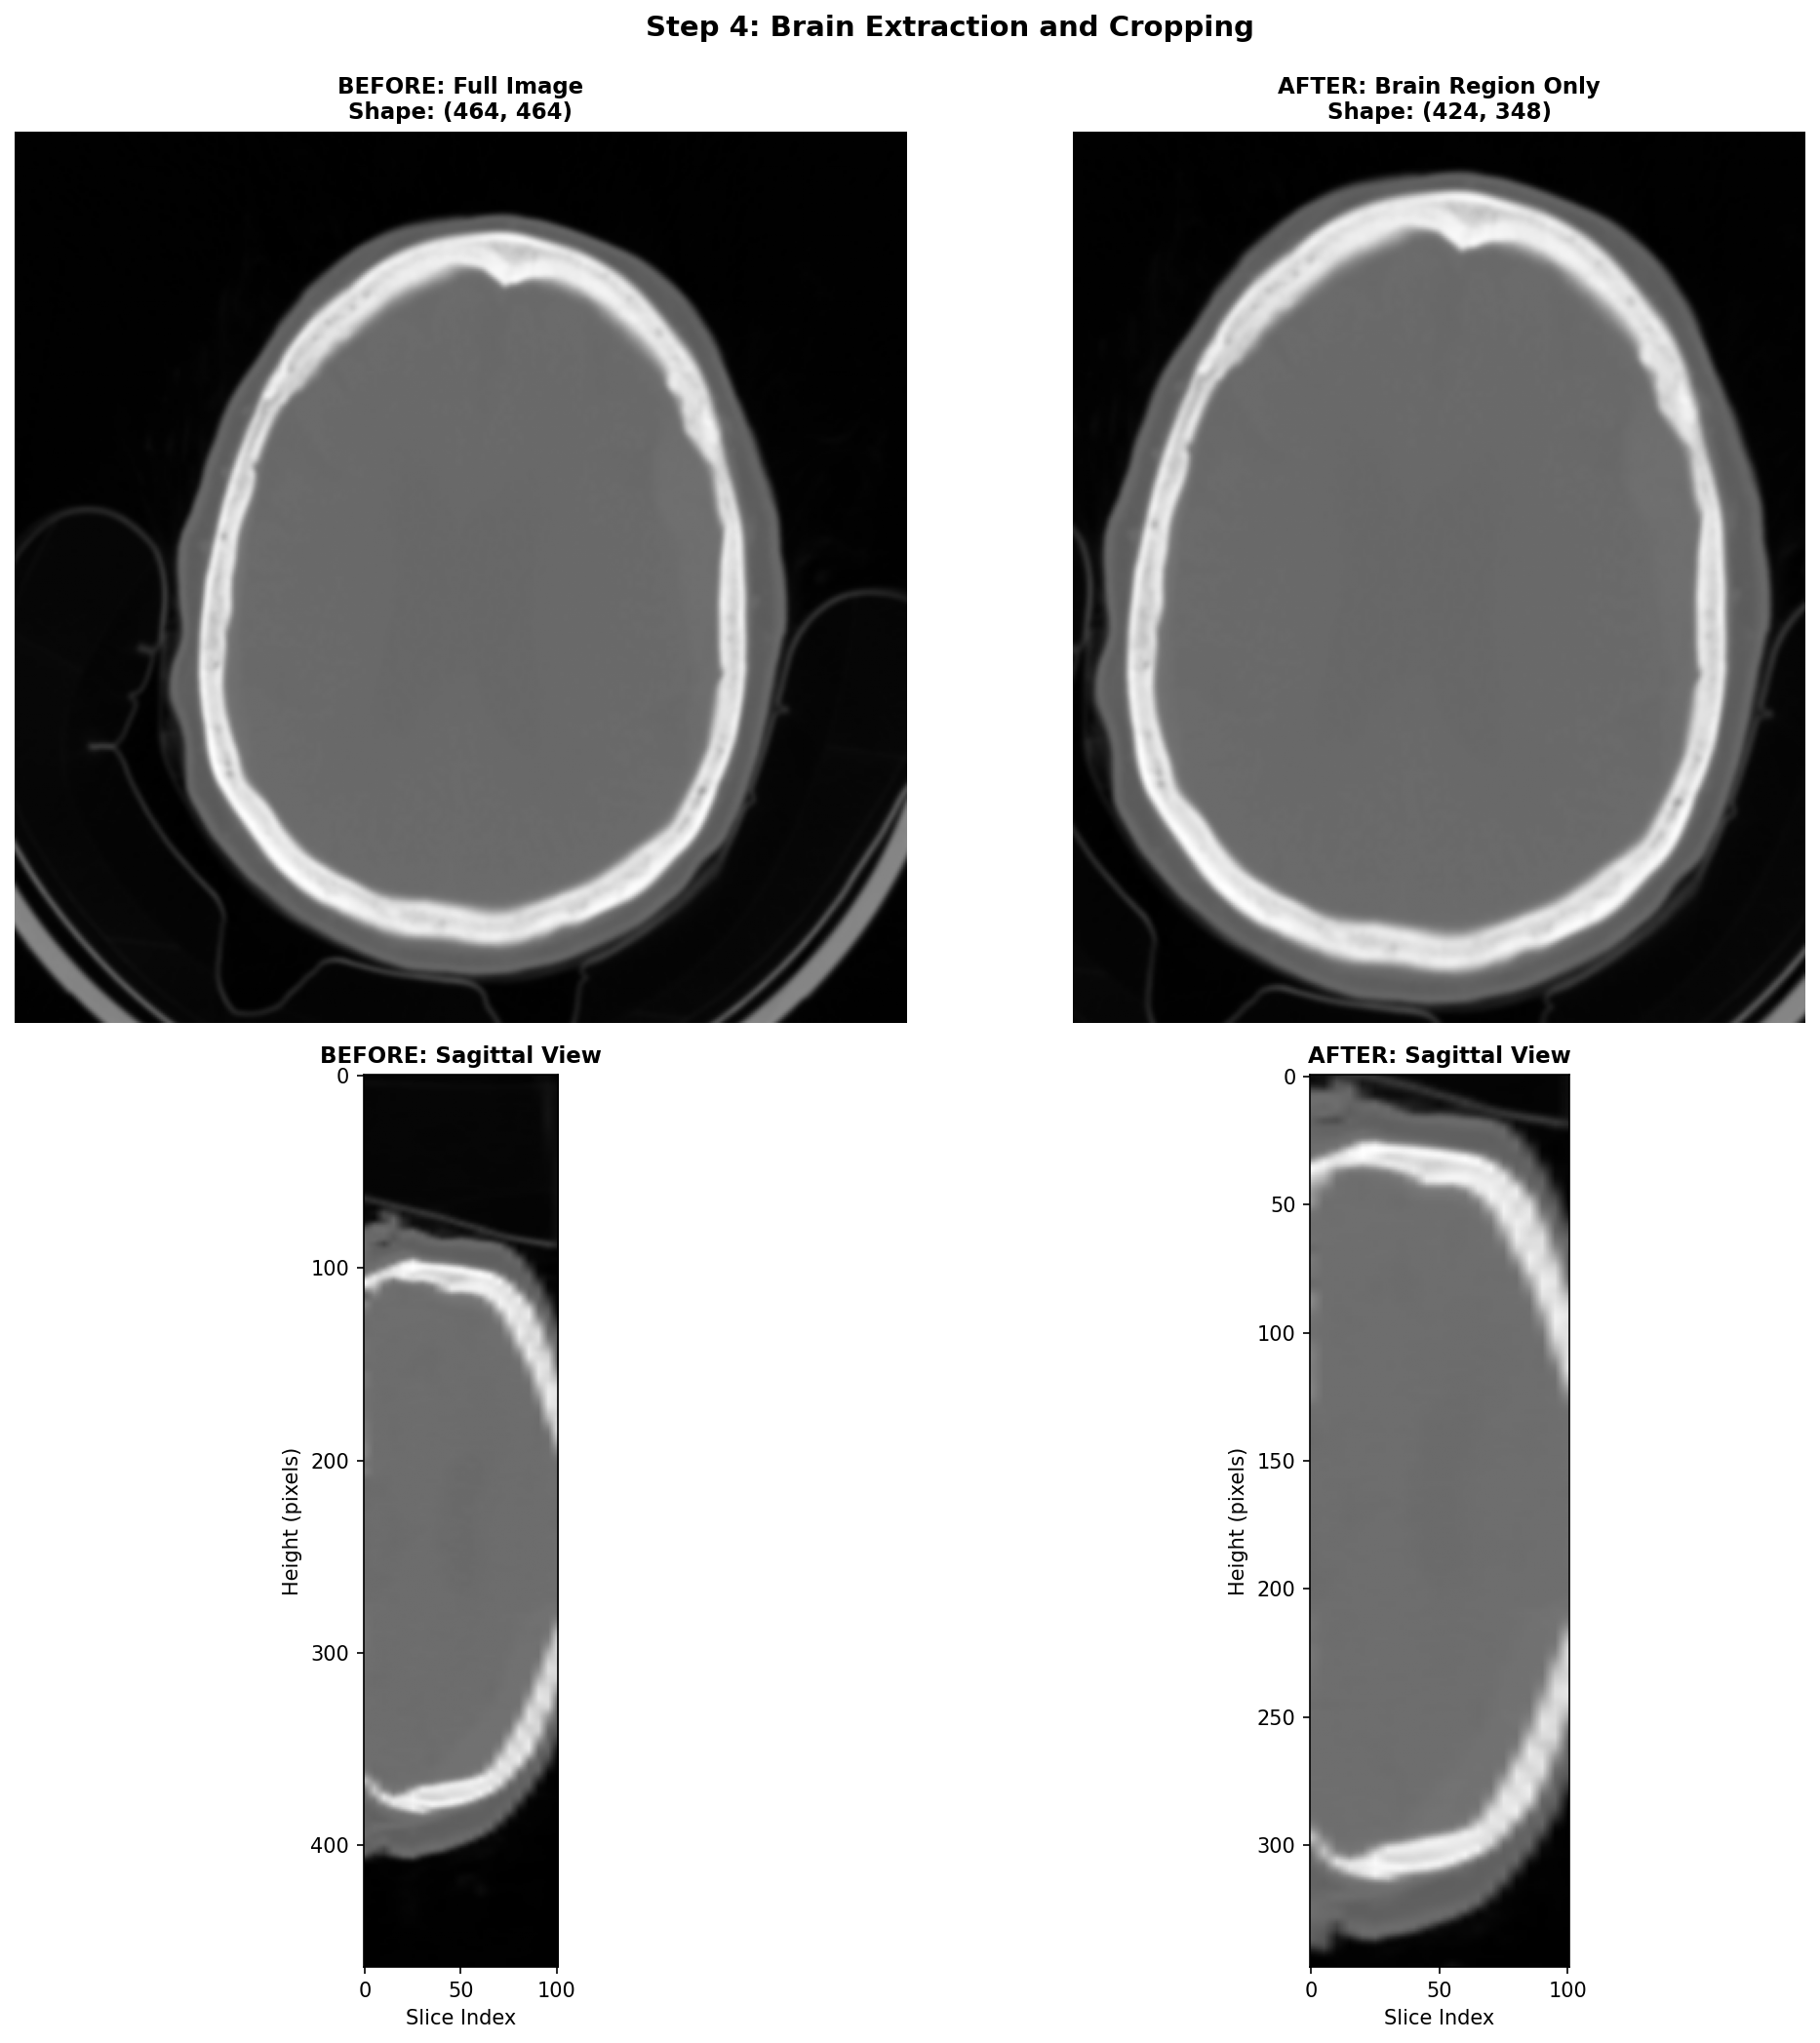

4) Brain Extraction and Cropping Techniques

When working with CT head scans, the images dealt with often are images that include not just the brain, but also the skull, scalp, neck tissues, and sometimes even scanner table or artefacts on the edges. For stroke detection, most of this extra information is irrelevant noise that can confuse our deep learning models and slow down training.

The most practical starting point for brain cropping leverages a fundamental property of CT imaging: brain tissue has a predictable range of intensity values. We can create a binary mask by simply keeping everything in the brain tissue range, and casting away the rest.

This simple approach is fast and can be effective for most stroke detection applications. Its main limitation is that it doesn't produce a true brain mask, it just finds a tight bounding box around brain-intensity tissues. If the need to use more sophisticated brain extraction methods arises, there are deep learning models like SynthStrip or the method by Liu et al. that can generate accurate brain masks. However, these methods require additional dependencies and computational resources, so they should be used only if the simple thresholding approach proves inadequate.

An important remark is that this step can be skipped if your application requires a fixed sized input size for your model, and so cropping the brain region and then padding to a fixed size is sometimes just equivalent to skipping this step and directly resizing the whole volume to the fixed size. As a general rule, always visualize the data through the whole processing pipeline to tailor it the best way possible to your specific task.

Here's how this works step-by-step:

- Create the mask: Keep only voxels with HU values in the brain range

- Select the brain: Use connected component analysis to keep only the largest connected region (the brain)

- Find the bounding box: Determine the smallest rectangular volume that contains all brain voxels

- Add margin: Expand the box slightly to avoid cutting off edge structures

Here, the brain cropping operation mainly removes artefacts related to the scanner table and some neck tissues.